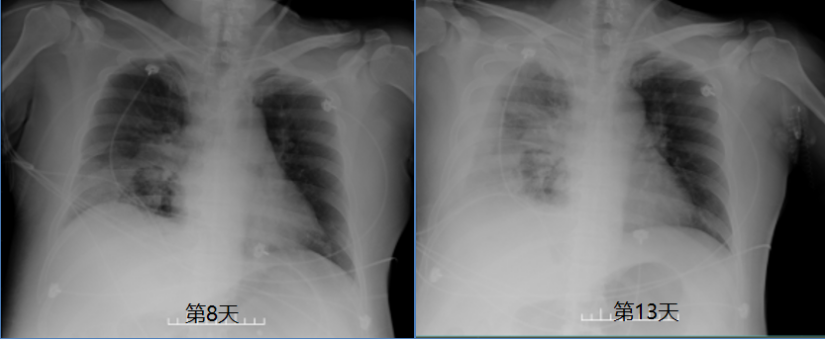

第2~8天随访胸部X线片示:肺部感染病灶范围稍减小

(图3)

图片

图3  患者胸部X线片

第13天随访胸部X片示:右侧胸腔少量积液;右肺门增大,右中下肺野病灶,较前稍加重(图11)

图11  复查胸部X线片